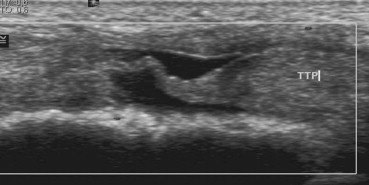

Imagen ecográfica de una rotura total del tendón tibial posterior

Y ahora, pasemos a cómo se ve una rotura total tendinosa en ecografía.

En este corte en eje largo, nos encontramos con una imagen muy visual de la rotura completa: la conocida como rotura en «chicle» (chewing gum).

Como puedes ver, el tendón tibial posterior (TTP) pierde por completo su linealidad y aparece con una forma tortuosa y ondulada, síntoma de que ha perdido toda su tensión mecánica y funcionalidad.

Ya no hay rastro de las fibras paralelas y brillantes. Lo que observamos es una estructura con irregularidades de calibre muy marcadas y una pérdida total de su organización fibrilar interna.